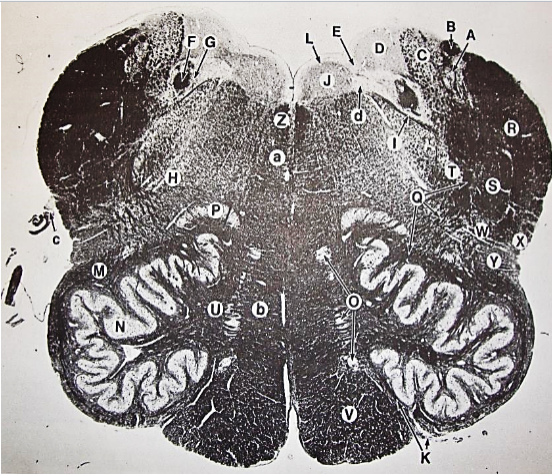

A

posterior median sulcus

B

posterior intermediate sulcus

C

anterior median fissure

D

gracile fasciculus

E

Gracile nucleus

F

fasciculus cuneatus

G

spinal trigeminal tract

H+I collectively

spinal trigeminal nucleus

J

Accessory nucleus

K

pyramidal decussation

L

lateral corticospinal tract

M

rubrospinal tract

N

posterior spinocerebellar tract

O

anterior spinocerebellar tract

P

lateral spinothalamic tract

Q

anterior spinothalamic tract

R

lateral vestibulospinal tract

S

medial longitudinal fasciculus

T

tectospinal tract

U

central canal